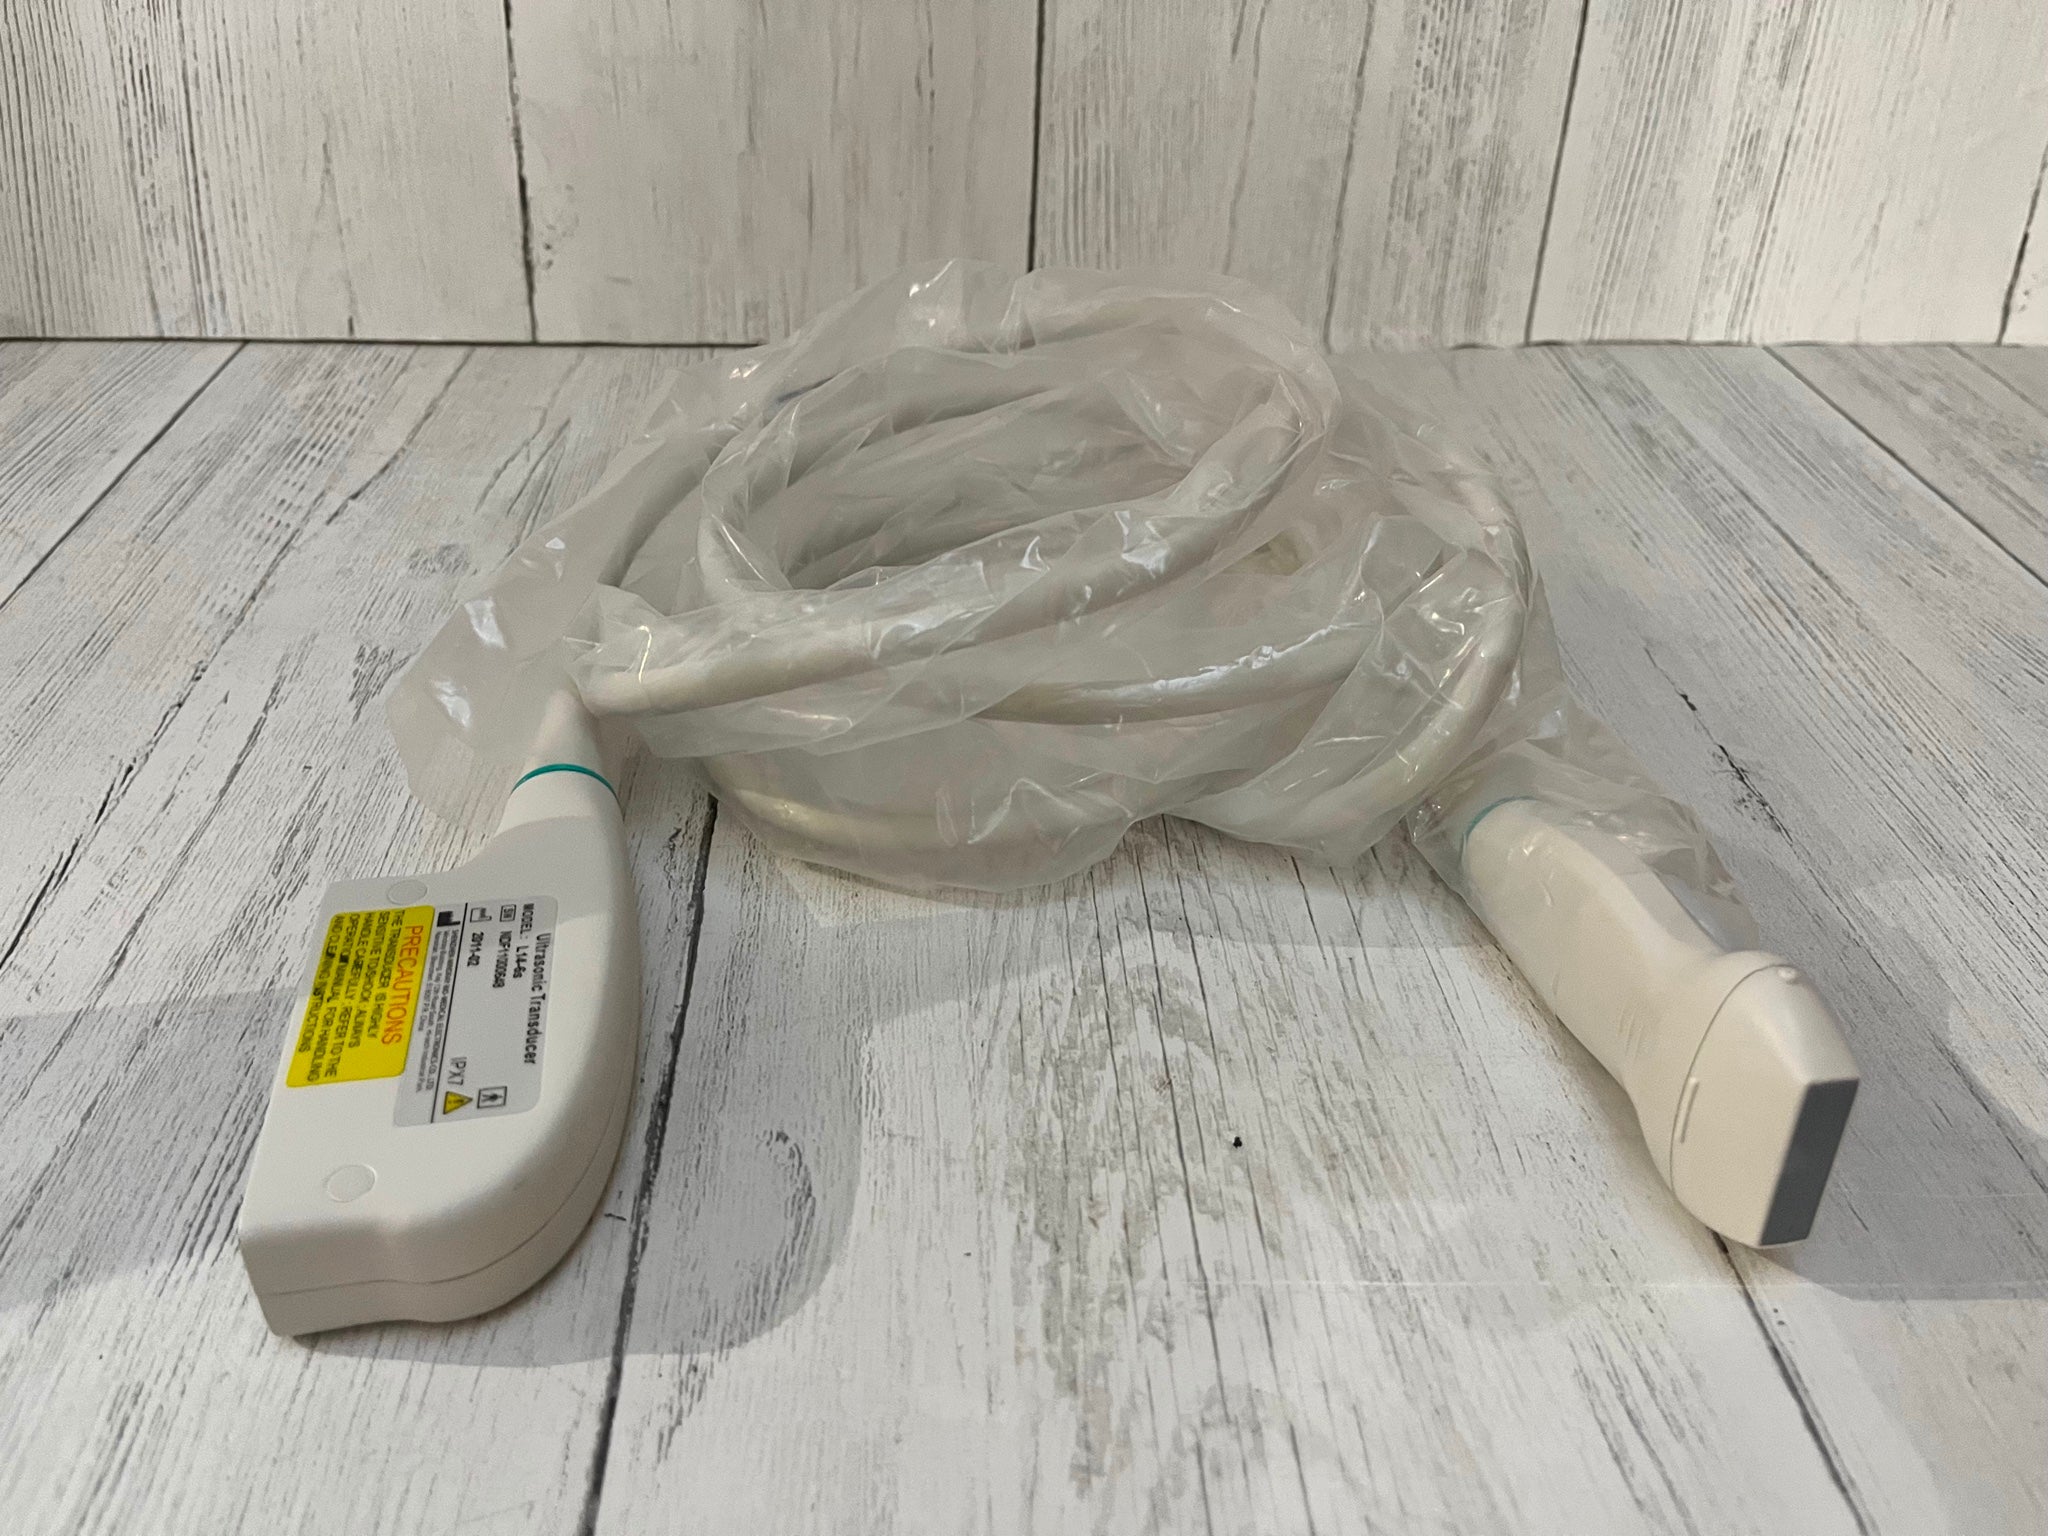

Micro-convex Probe |

Linear Abdominal |

Convex Probe |